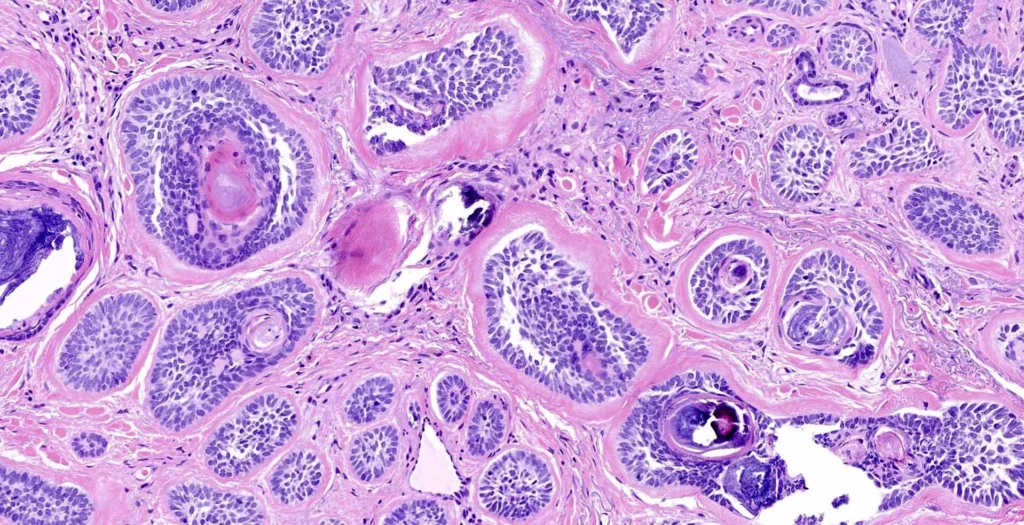

Аденокарциноми грудей – це ракові пухлини молочної залози, які розвиваються із залозистої тканини. До цієї групи належить близько 90% всіх злоякісних новоутворень грудей, що зустрічаються у жінок та дуже рідко – у чоловіків, найчастіше діагностуються у пацієнтів похилого віку.

Аденокарциноми класифікують за кількома ознаками. Одна з них – це ступінь диференціації клітин:

- високодиференційована аденокарцинома молочної залози – складається з клітин, які за будовою дуже схожі на здорові, поділяються відносно рідко, рідше відбувається метастазування, що обумовлює більш сприятливий прогноз для пацієнта;

- помірно диференційована аденокарцинома молочної залози – клітини мають менший ступінь диференціації та частіше поділяються, що призводить до більш агресивного перебігу хвороби;

- низькодиференційована аденокарцинома – пухлина, клітини якої сильно відрізняються від здорових, часто поділяються, внаслідок чого новоутворення швидко зростає, поширюється на оточуючі тканини і метастазує в інші органи.

Залежно від того, з клітин якої структури розвинулася пухлина, розрізняють:

- інвазивні та неінвазивні протокові аденокарциноми (з клітин молочних протоків);

- інвазивні та неінвазивні долькові аденокарциноми (з клітин дольок молочної залози).

Особливий тип пухлини – скірозна аденокарцинома, у будові якої переважають стромальні елементи (це сполучна тканина, нерви, судини), а пухлинних клітин небагато і вони розташовані між ними ланцюжками.